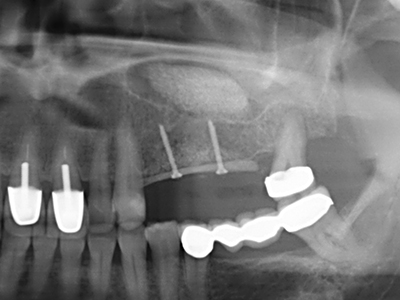

Die Präparation des lateralen Fensters bei der externen Sinusbodenelevation stellt gerade für chirurgisch unerfahrene Implantologen eine große Herausforderung dar. Die knöcherne Bedeckung der Kieferhöhle ohne eine Verletzung der darunterliegenden Schneider’schen Membran abzutragen ist dabei nur ein Teil der Operation – nach Schaffung eines ausreichenden Zugangs muss die Kieferhöhlenschleimhaut vorsichtig mobilisiert werden, um Raum für das einzubringende Material bzw. die Implantate zu schaffen. In dieser Indikation ist die Piezochirurgie zweierlei hilfreich: zum einen kann durch Verwendung diamantierter Instrumente eine selektive Knochenabtragung erfolgen und die darunter liegende Schleimhaut bleibt bei vorsichtiger Vorgehensweise intakt. Zum anderen unterstützen die Ultraschallfrequenzen zusätzlich eine komplikationslose Ablösung der Schleimhaut – sie werden durch spezielle stumpfe Ansätze in den Spaltraum zwischen Schleimhaut und Kieferhöhlenboden übertragen (Cassetta, Ricci et al. 2012, Pereira, Gealh et al. 2014) (Rickert, Vissink et al. 2013). So erscheint es nicht verwunderlich, dass in aktuellen Übersichtsarbeiten über die externe Sinusbodenelevation neben der Verwendung von rauen Implantatoberflächen und dem Einsatz von Knochenersatzmaterialien auch der Einsatz von piezoelektronischen Geräten als positiv bewertet wird (Wallace, Tarnow et al. 2012).

Sollen chirurgische Eingriffe mit unmittelbarer Knochenbeziehung an empfindlichen Strukturen wie Blutgefäßen oder Nerven erfolgen, so bergen rotierende Instrumente ein erhebliches Potential an iatrogener Schädigung. Gerade bei Nervdarstellungen nach iatrogener Schädigung, oder aber im Zuge einer Nervlateralisation für resektive und rekonstruktive Eingriffe oder Implantatinsertionen können piezoelektronische Geräte hilfreich sein Knochendeckel zu präparieren und nervnahe Hartgewebsanteile zu entfernen (Abb. 17-20). Ein leichter Kontakt des Nervstrangs zur Piezospitze bleibt dabei in der Regel folgenlos – allerdings kann eine unvorsichtige Vorgehensweise mit sägeartigen Bewegungen bzw. Ansätzen bei noch vorhandener knöcherner Unterlage durchaus temporäre oder aber auch permanente Nervschädigungen verursachen. Das Risiko einer solchen Schädigung wird jedoch als wesentliche geringer eingeschätzt als unter Anwendung von Säge- oder Fräsinstrumenten (Pereira, Gealh et al. 2014).

Wie sich in der Vergangenheit gezeigt hat stellt prinzipiell jeder knochenchirurgische Eingriff eine mögliche Indikation für die Piezochirurgie dar. So lässt sich die Präparation des mobilen Segmentes bei der Distraktionsosteogenese (Abb. 23-25) und der Sandwichosteotomie mit speziellen Ansätzen bewerkstelligen, ohne die für den Erfolg beider Techniken essenzielle Blutversorgung des krestalen Anteils zu gefährden (Gonzalez-Garcia, Diniz-Freitas et al. 2008).